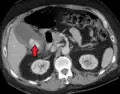

Acute cholecystitis as seen on ultrasound. The closed arrow points to gallbladder wall thickening. Open arrow points to stones in the GB -

Acute cholecystitis with gallbladder wall thickening, a large gallstone, and a large gallbladder -